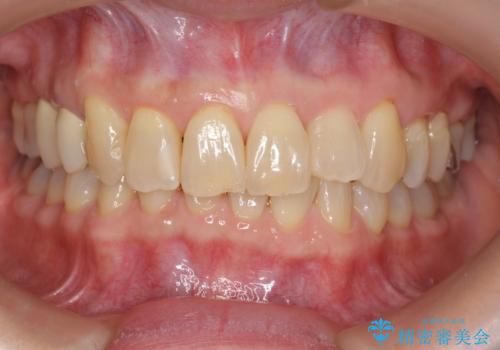

前歯のクロスバイトと治療が必要なむし歯 矯正とセラミックの総合歯科治療